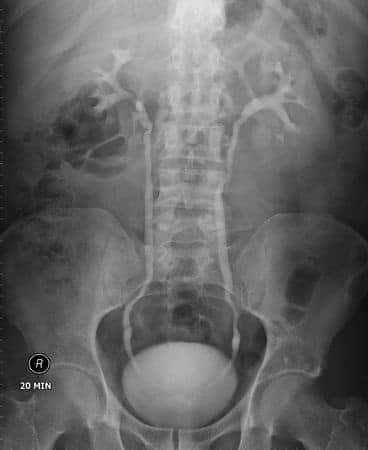

This case involves a fifty-three-year-old patient who presented to his urologist complaining of recent sexual dysfunction. He also complained of sleep disturbances, fatigue, and lower back pain. The urologist advised the patient that he may be suffering from low testosterone and would likely benefit from using AndroGel “trt,” or therapeutic testosterone cream. The physician only performed a physical exam on the patient but neglected to screen his blood for a baseline PSA value. Three months later, the patient returned with reports of improved sexual function but now complained of new urinary symptoms associated with occasional blood in the urine. Subsequently, the patient was found to have advanced prostate cancer.